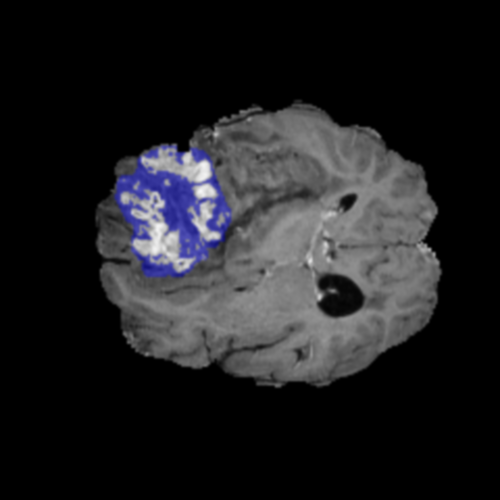

Ejemplos de Modalidades MRI

Visualización de las 4 modalidades de resonancia magnética y las segmentaciones de zonas tumorales utilizadas para entrenar el modelo

Glioma de Alto Grado (HGG)

FLAIR HGG

FLAIR

T1ce HGG

T1ce

T2 HGG

T2

T1 HGG

T1

Núcleo HGG

Núcleo

Edema HGG

Edema

Realce HGG

Realce

Tumor Completo HGG

Tumor Completo

Núcleo Edema Realce